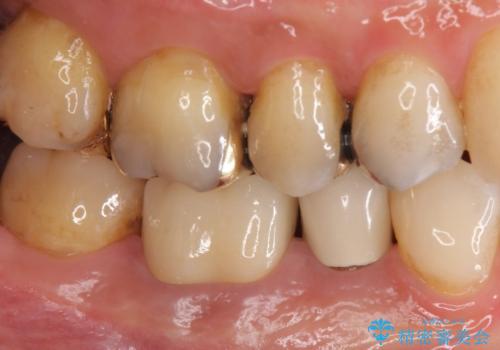

- 右下6 仮歯+ジルコニアクラウン 11,000円+121,000円費用は治療当時の料金となります

気になっていた銀歯を自然な色に変えることができ、大変喜んでいただけました。